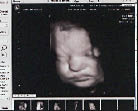

Правда, в любых правилах есть исключения: и среди эмбрионов встречаются те, кто любит попозировать. Одного такого зазвездившего мальца Голентовский отснял почти сразу же после приобретения аппарата.

- Мы про себя назвали его пляшущим мальчиком, - смеется врач. - На экране четко видно, как малыш, окруженный околоплодными водами, совершает движения, похожие на танец: ударяет ручками по стенкам матки, пошатывается, коленца выкидывает. Эмбриону - 12

недель. Нам очень повезло. Таких четких кадров больше получить не удалось.Однако будущая дочь Насти и Саши Бреус явно не разделяет желания своих сверстников покрасоваться перед УЗИ: с большим трудом гинеколог смог поймать кадр, на котором четко видны головка и две малюсенькие ручки.